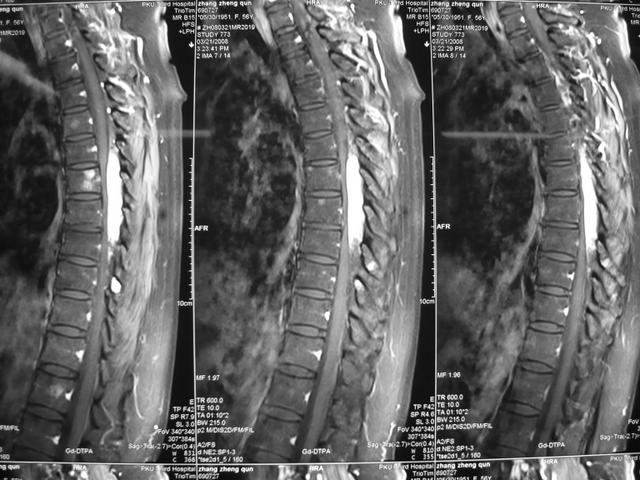

罕见血管脂肪瘤